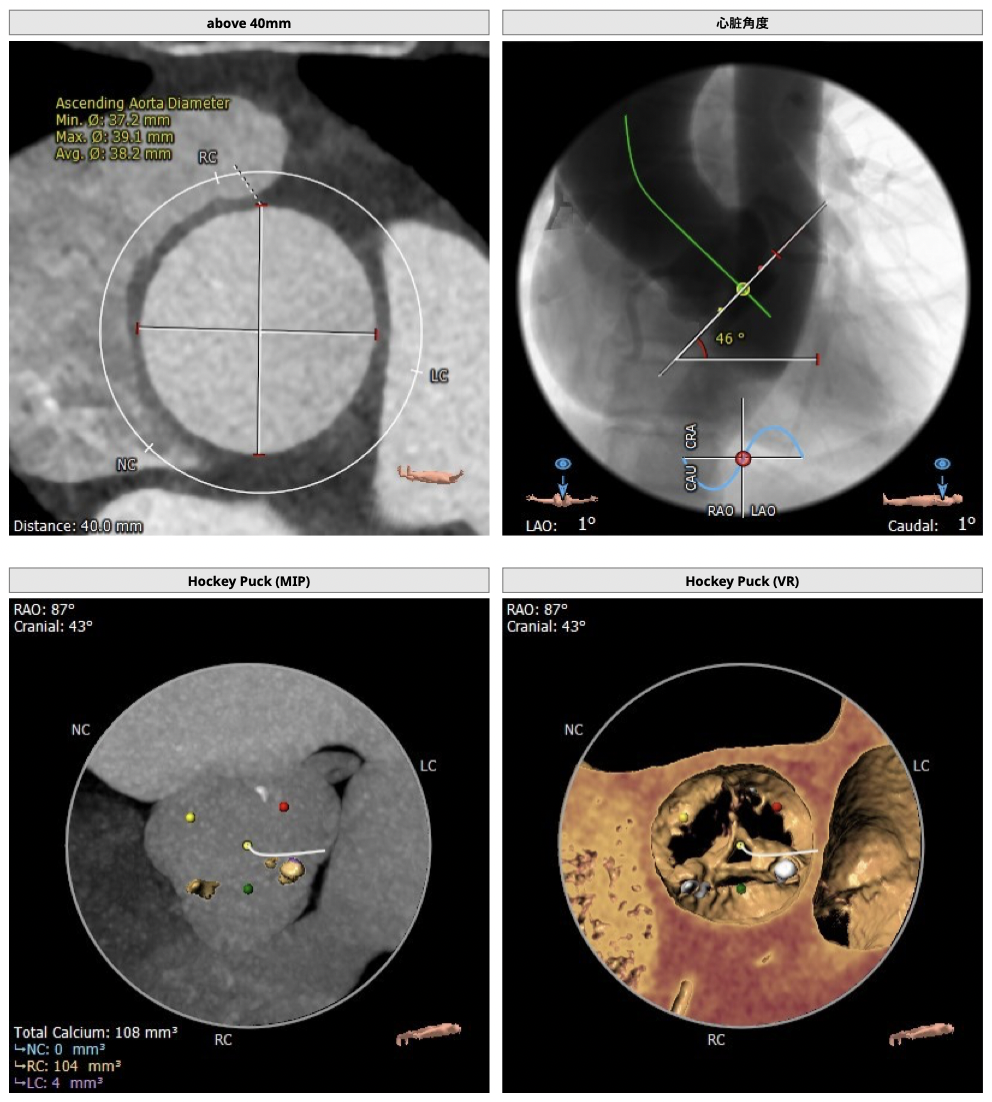

主动脉CT

难点分析:

*患者为TYPE1型二叶瓣,左右融合,重度钙化,融合脊难以推开,瓣膜释放后具有一定瓣周漏风险;

*心脏角度为60°,横位心,输送器过瓣难度增加,瓣膜植入同轴性差,瓣膜释放更易移位,增加了操作的难度;

*髂动脉走形迂曲,升主动脉明显扩张,术中操作需轻柔;

制定策略:

经分析研判,拟从右侧股动脉穿刺入路,使用23mm球囊预扩,采取downsize手术策略,选用L26号的VenusA-Valve瓣膜,因患者为横位心,瓣膜释放同轴性差,容易发生移位,故采用VenusA-Plus可回收输送系统确保瓣膜的稳定释放,瓣膜释放后结合造影和超声情况,决定是否后扩。